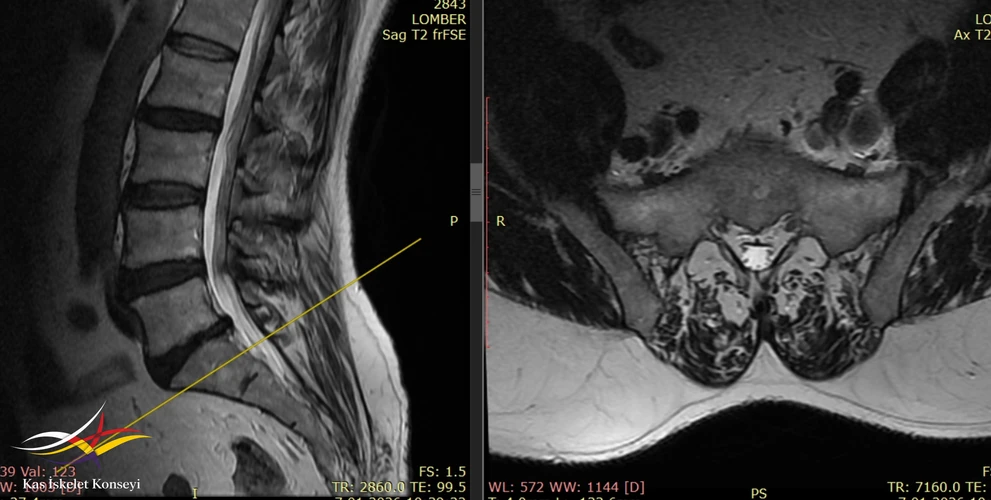

İncelemeler: Lomber MRG de L5-S1 santral disk hernisi mevcuttu. Solda korpus ön komşuluğunda iliak ven genişlemiş görünüyordu (Resim). Yapılmış olan EMG incelemesinde solda "L3-L5 spinal ganglion proksimalinde tutulum" rapor edilmişti.

Resim 3. Lomber MRG'de L5-S1 disk hernisi görülmekte. Sol iliak ve korpus ön komşuluğunda dilate görünümde.

Resim 4. Lomber MRG, daha kaudal kesitte sol iiak arter ve ven ilişkisi görülmekte.